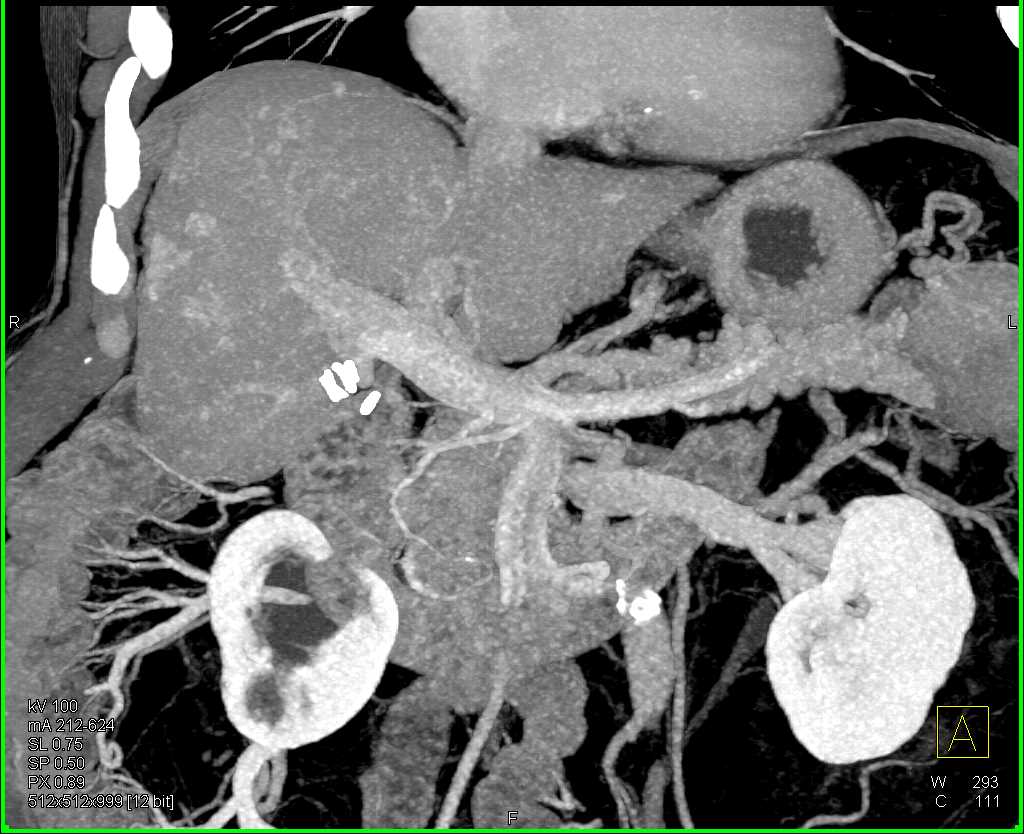

Hepatoma in Cirrhotic Liver